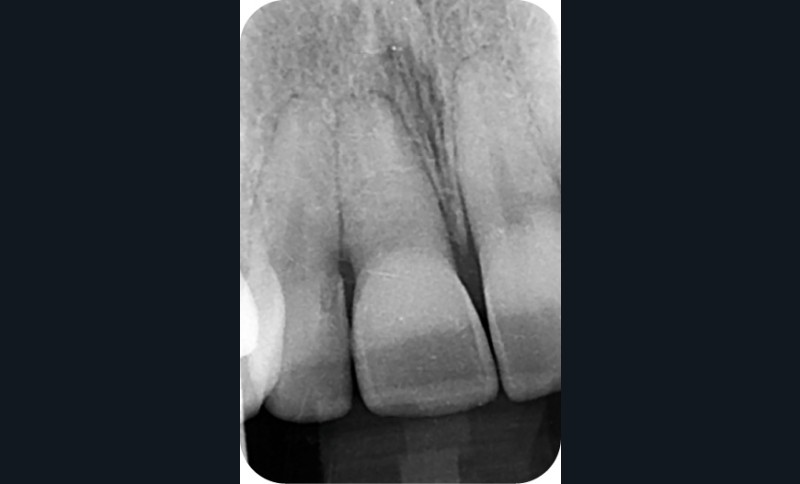

– Traumatismes (fig. 5a, b).